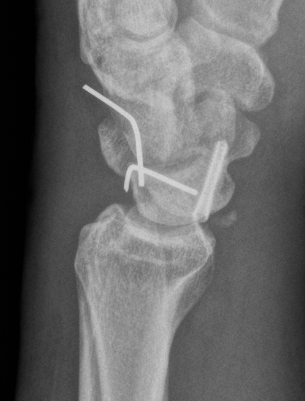

CT

Trans-scaphoid perilunate dislocation

Perilunate dislocation